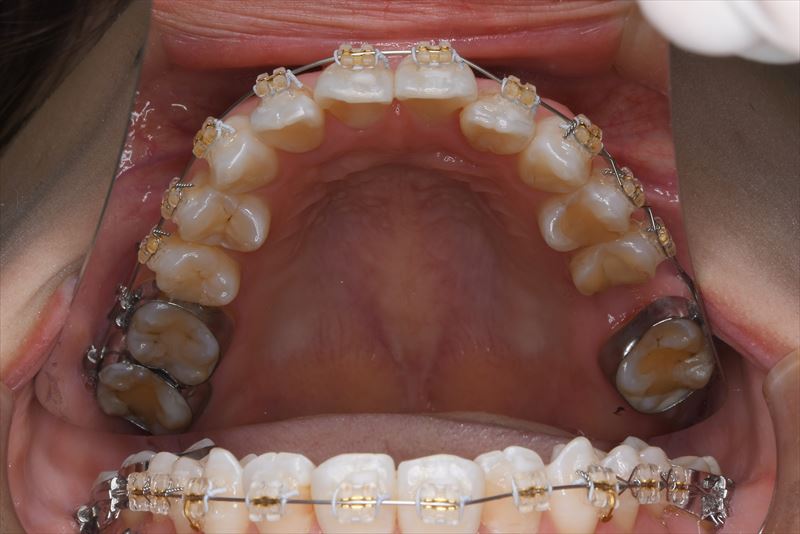

治療中

- 両側2番クロスバイト、叢生、上顎左側6番根尖病巣

- マルチブラケット装置、アンカースクリュー

- 上顎左側6番抜歯

- 上顎左側6番は失活歯で根尖病巣を認めたため抜歯し、上顎左側8番を代わりに使用することとしました。アンカースクリューを使用することにより、健康な歯を抜歯せず臼歯の遠心移動で叢生の改善できました。治療期間が短かく良好な咬合を獲得できました。